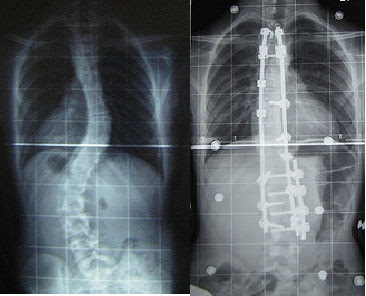

Scoliosis atau dari bahasa Yunani skolios (bengkok) adalah suatu keadaan di mana tulang belakang seseorang yang melengkung dari sisi sama ada ke kiri atau ke kanan. Jika lihat melalui x-ray, tulang belakang individu scoliosis kelihatan lebih seperti "S" atau "C".

Gambar hiasan dari wiki: Sebelum dan selepas pembedahan Scoliosis

Setelah lama tunggu waiting list yang panjang berjela tu, 25 mac 2009 saya menjalani pembedahan selama 8 jam. Hari ke 3 lepas pembedahan saya tersedar dan tengok-tengok dah kat ICU. Hari ke 5 baru masuk wad biasa, belajar bernafas, belajar berjalan, belajar bersenam, belajar pakai baju dan belajar duduk semua. Macam bayi pon ade, siap pakai lampin lagi. Saudara mara semua datang tengok saya, rasa gembira sangat masa tu. Paling saya terharu kawan-kawan kelas (DAS 6 sem ni) datang jauh-jauh dari Sabak Bernam tengok saya. Dah la diorang sesat-sesat, terharu sangat-sangat. Kawan-kawan lain pon datang juga, KKA bagi sumbangan terima kasih sangat.

Sekarang saya sudah sihat sepenuhnya. Boleh lari-lari, lompat-lompat, berenang, semua boleh dah cuma angkat berat je tak boleh. Rasa kejang kat kaki sampai sekarang rasa lagi, lebih-lebih lagi masa peperiksaan. Kalau masa hujan, rasa nyilu ada, sejuk pun ade. Mana taknya, besi titanium dalam badan, rod panjang 2 batang dengan 14 biji skru. Haha bionik tak?